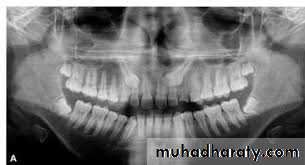

Classification of impacted lower third molar

1- Pell and Gregory classification according to the depth or according to the relation of the impacted tooth to the occlusal plane of the lower second molar

2- Pell and Gregory classification according to the relation ship of the lower second molar to the anterior border of the ramus

3- Winters classification according to the angulations of the long axis of the impacted tooth

Relation of the impacted tooth to the anterior border of the ramus

Class 1 : the space between the lower second molar and the anterior border of the ramus is sufficient to accommodate the mesio distal dimension of the crown of the impacted lower third molarClass 2 : the space between the lower second molar and the ramus is insufficient to accommodate the crown of the impacted tooth .so part of it in the body and the other part lie in the ramus .

Class 3 the anterior border of the ramus lie near the distal surface of the lower second molar ,so ,the whole impacted tooth lie within the ramus .

Winters classification of impacted lower third molarMesio angular

Disto angular

Horizontal

Vertical

Inverted

Transverse

Buccoversion

Linguversion